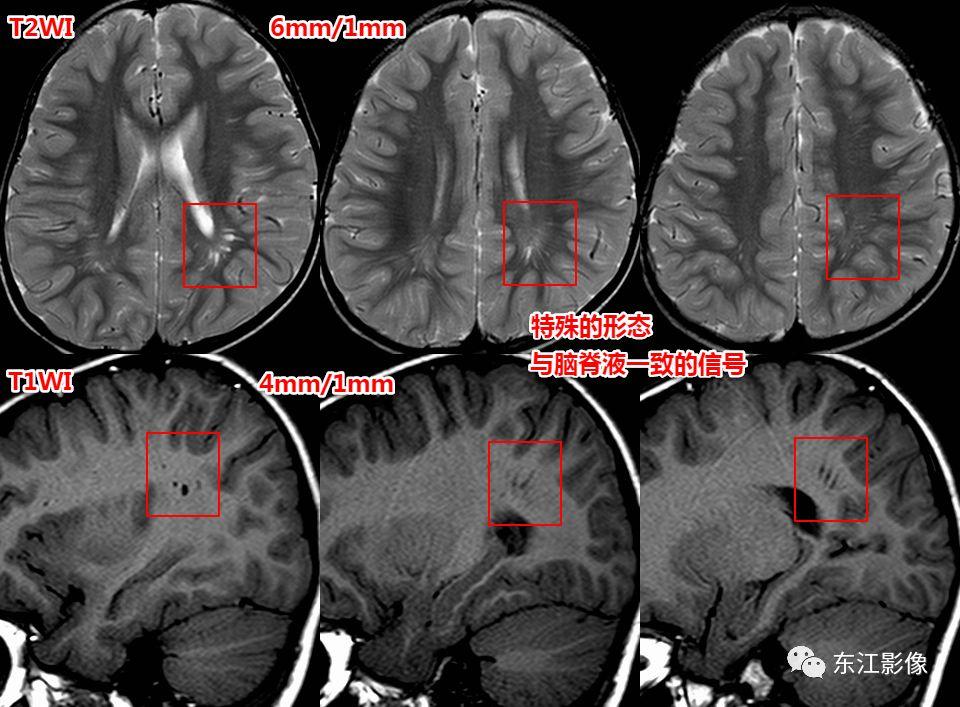

形态

- 纺锤样,泪滴状。

信号

- 与脑脊液一致。

侧脑室顶区周围白质也是VRS的常见部位。